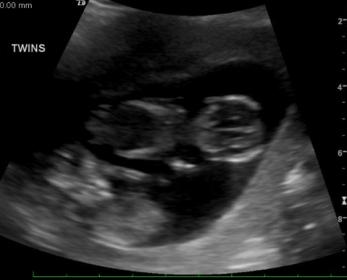

This isn't a gender question, so I apologize if there is a better place to put this - NBP feel free to move it if it belongs elsewhere. These are my twins at 10w (although they are measuring more like 9w5d). I'm worried the line between them looks thin - does anyone have an opinion if they look like di/di or mono/di ? I was too in shock when my OB told it was twins to ask any questions and I don't go back for a real ultrasound until 15 weeks.